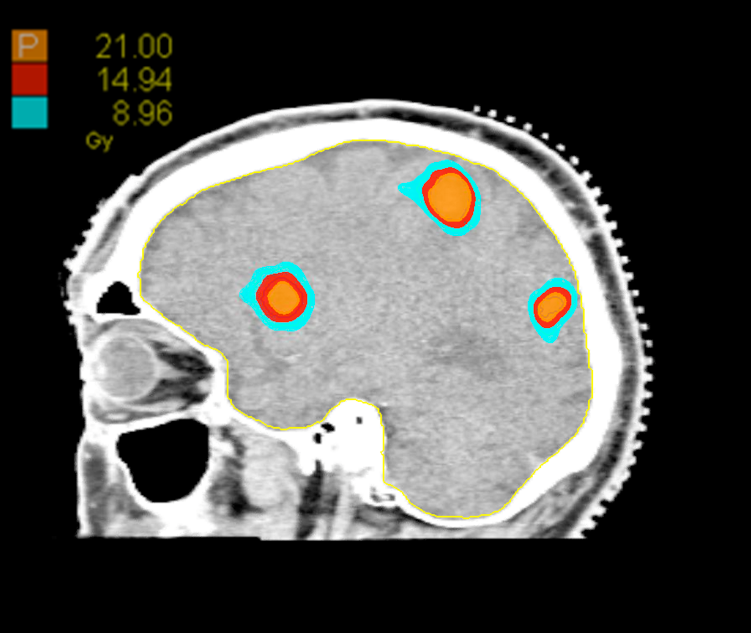

Treatment Plan Images

Dose Distributions

- Prescription to the 70.3% isodose line

- Max. dose 29.9 Gy